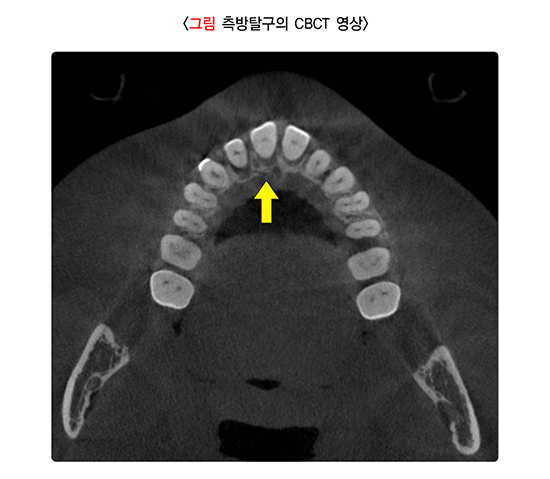

치아외상이 발생한 경우 치아의 파절, 변위(위치의 변화)뿐 아니라 뼈의 골절, 타박상, 찰과상, 열상 등 연조직 손상이 동반될 수 있으므로 면밀한 검사가 필요합니다. 임상 사진으로 외상 초기의 상태를 기록하여 연조직 치유, 치아 변색, 빠져 들어간(함입) 치아의 재맹출 및 유착, 치아의 저위 교합 등을 평가, 관찰합니다. 방사선 사진은 치아 외상을 정확히 진단하기 위해서 뿐만 아니라 치료법 선택에 필요한 정보를 제공하며, 후속 검사에서 비교 기준을 제공하므로 반드시 필요합니다. 콘빔형 전산화단층영상(cone-beam computed tomography, CBCT)은 치근 파절, 치관-치근 파절, 측방 탈구에 대해 효과적인 시각 자료를 제공합니다. 골절의 위치, 범위 및 방향을 평가하는 데도 도움이 됩니다. 그러나 어린이는 방사선 노출을 최소화하기 위해 정확한 진단 및 치료에 필요한 최소한의 촬영을 권장합니다. 치수 민감도 검사는 치수 상태를 평가하는 데 사용되는 냉온 검사 및 전기 치수 검사를 포함하며, 치아외상 후 시간에 따른 변화를 확인하기 위해 초기와 후속 검사에서 모두 필요합니다.